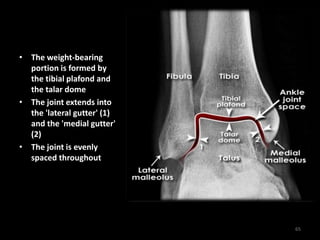

• The weight-bearing

portion is formed by

the tibial plafond and

the talar dome

• The joint extends into

the 'lateral gutter' (1)

and the 'medial gutter'

(2)

• The joint is evenly

spaced throughout